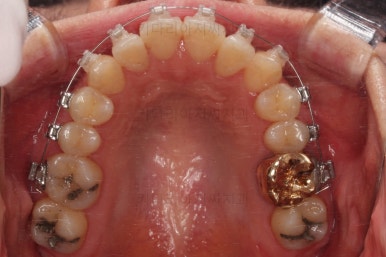

초진 시, 입안의 모습입니다.

좌측 송곳니가 덧니처럼 튀어나가 있고, 송곳니 옆의 작은 억므니가 안으로 쏙 들어가서 덧니 느낌이 더 강조되어 보이네요.

위아래 앞니가 긴밀하게 겹침이 없는 약간의 개방교합(오픈바이트, Openbite) 경향이 보입니다.

이번에 선택하신 장치는 자가결찰 세라믹 중에 엠파워 클리어라는 장치인데요.

흔히들 아시는 클리피씨도 같은 분류의 장치입니다.

철사가 들어가니 삐뚤한 치열이 더 강조되어 보이네요.